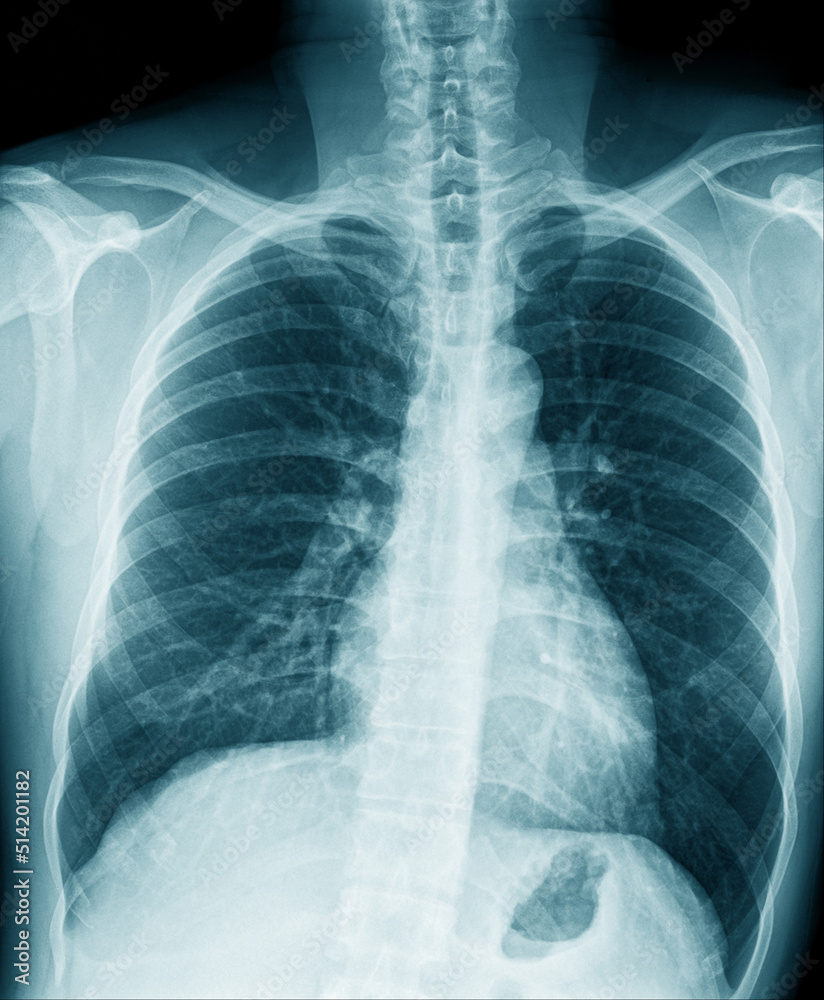

chest x ray Ray chest human healthy stock depositphotos

www.bigstockphoto.comChest X-ray Image In Blue Tone Stock Photo | Adobe Stock

www.bigstockphoto.comChest X-ray Image In Blue Tone Stock Photo | Adobe Stock

stock.adobe.comX-Ray Image Of Human Healthy Chest — Stock Photo © Jovannig #11802437

stock.adobe.comX-Ray Image Of Human Healthy Chest — Stock Photo © Jovannig #11802437

depositphotos.comray chest human healthy stock depositphotos

depositphotos.comray chest human healthy stock depositphotos